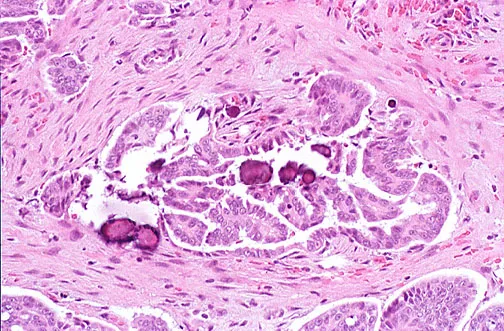

- Serous: Most common (~30% of all ovarian tumors, 40% of malignant). Psammoma bodies. Often bilateral.

⭐ Serous tumors are the most common malignant epithelial ovarian tumors, and BRCA1/2 mutations significantly increase risk, particularly for high-grade serous carcinoma (HGSC).